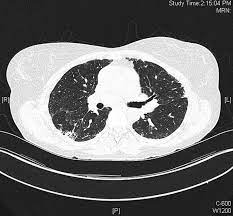

Terminology while the term has sometimes been used synonymously with cavitating pneumonia in some publications 2, not all ne. An acute granulomatous interstitial pneumonitis occurring in agricultural workers. 2) focal necrotizing or granulomatous vasculitis of small. Necrotizing pneumonia is characterized by necrosis and liquefaction of consolidated lung tissue, which may be complicated by solitary, multiple, or multiloculated radiolucent foci, bronchopleural fistulas, and intrapulmonary abscesses. Mimicking hypersensitivity pneumonitis as an uncommon initial presentation of chronic granulomatous disease in children.

Necrotizing pneumonia is characterized by necrosis and liquefaction of consolidated lung tissue, which may be complicated by solitary, multiple, or multiloculated radiolucent foci, bronchopleural fistulas, and intrapulmonary abscesses. Fever, dyspnea, cough, crackles monocytosis in bronchoalveolar lavage. Necrotizing sarcoid granulomatosis (nsg) is a granulomatous disease entity which presents with nodular masses of sarcoid like granuloma which primarily effects the lungs. These need to be distinguished from other granulomatous processes such as wegener's granulomatosis (wg). © 1999 lippincott williams & wilkins, inc.